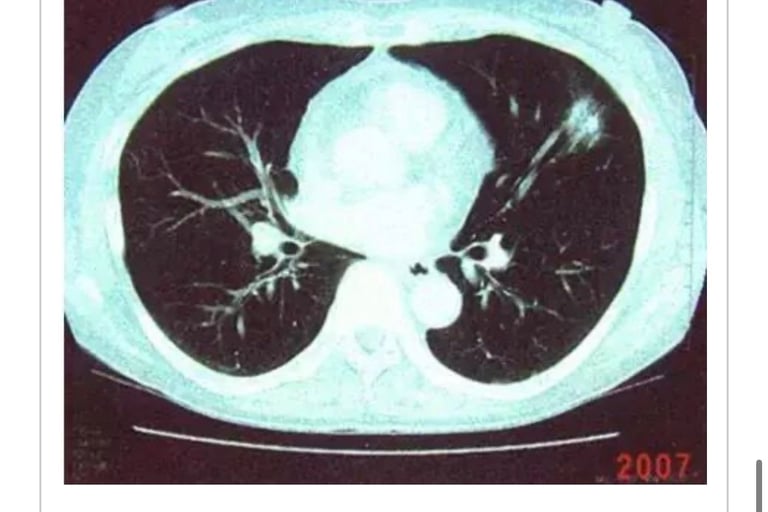

(2006.3⇒2012.12)(再发) S・S(1945年生、女性)

2005年4月6日、左肺癌(多发性器官癌=pT1pNOMOStage1A)左肺上叶切除。1年后再发。被称为「无良好治疗方法」(照片1)。

2006年3月24日到我院就诊。患者体征为轻度呼吸困难。就诊当日开始微波照射治疗,至9月中旬合计照射46次,较初期5月治疗时身体舒适可以做深呼吸。

2006年7月7日CT检查显示再发消失。

2009年8月至今,血液检查指标正常,无特殊症状。

2009年1月9日CT检查显示无异常变化(照片2)。同年12年12月来院复查。情况良好。